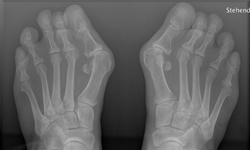

拇指外翻的特徵是大拇趾偏向第2根腳趾,第1蹠骨偏向內側,且形成骨狀突出物,圖片是拇指外翻的X光圖。

先讓大家看X光照壓壓驚,等你做好了心理準備,我們再來看看當彩色的拇指外翻圖!